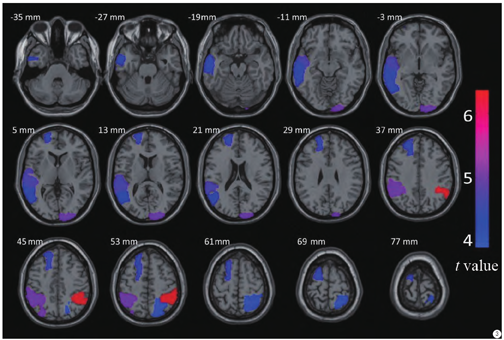

与正常对照组比较,虽然自闭症儿童平均年龄更小,但在额叶、顶叶、枕叶、颞叶、楔前叶部分的皮层厚度显著高于正常儿童,表现出和年龄相关的大脑异常发育(图1,第1~2行)。同时,自闭症儿童在右外侧枕叶、右侧顶上区、左侧颞中回、右侧额下回三角部的脑体积显著高于正常人(图1,第3行),在小脑、脑干和杏仁核部分,自闭症儿童的数值低于正常儿童。

通过对FreeSurfer计算得到的结果进行t检验分析,结果见图2和图3,自闭症与正常儿童皮层厚度差异最大的部位集中于双侧顶下小叶、右侧枕叶、右侧额上回、左侧额中回上部以及左侧颞中回。